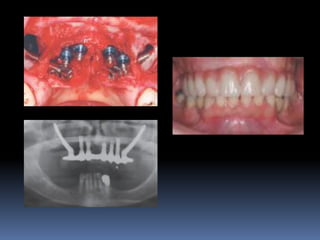

Exames Imaginológicos

Radiografias periapicais, telerradiografias e

panorâmicas;

Tomografias computadorizadas

Softwares de imagens 3D